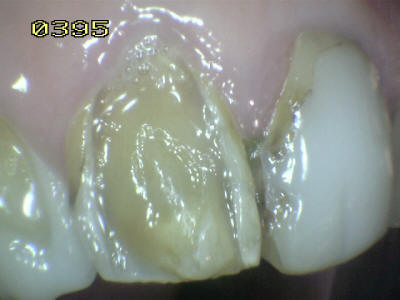

Paciente de sexo femenino de 60 años de edad, que a la inspección clínica se observa perdida de esmalte por erosión ácida en los dientes antero-superiores. Durante el interrogatorio el paciente cuenta que ingiere grandes cantidades de limón y naranjas naturales. Este habito dietético ocasiona erosión ácida por el contenido de acido cítrico que contienen dichas frutas.

Note en las imágenes inferiores el deterioro extenso del esmalte, que lleva en algunos sitios a la exposición de la dentina. Como el proceso es gradual el paciente no tiene sintomatología dolorosa al estímulo térmico.

Este tipo de lesión es clasificada en una escala de leve, moderada y grave, como grave y debe ser tratada con recubrimientos estéticos a base de resina o porcelana. El no tratar estas lesiones puene llevar a producir caries dentinaria con la pérdida de las piezas dentales. Otra acción a  tener en cuenta es la posibilidad de un cambio en la dieta, basado en la disminución de la frecuencia de la ingesta del limón y naranja.

Observe como se ha perdido la estructura dental en 13, 12 y  en 11 una carilla en resina compuesta  donde se ha deteriorado el borde cavo superficial de la misma. En 23 el mismo patrón de desmineralización dental